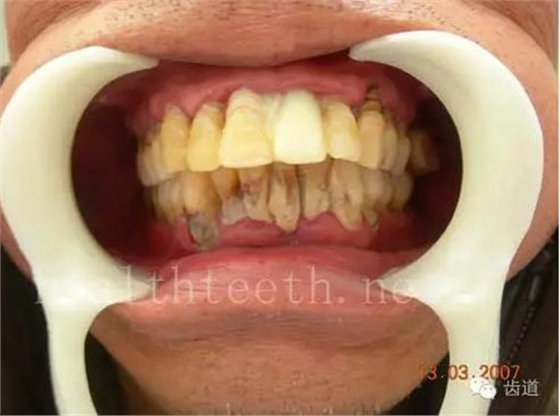

青少年牙周炎,20多歲牙齒破壞到這個程度